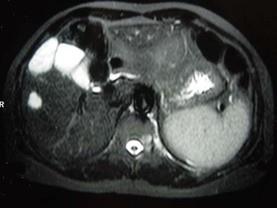

请结合提供图像,选择最佳选项 ( )A、退行性变B、脂肪瘤C、多发性骨转移D、骨血管瘤病E、骨结核

问题 请结合提供图像,选择最佳选项 ( )

选项 A、退行性变 B、脂肪瘤 C、多发性骨转移 D、骨血管瘤病 E、骨结核

答案 D